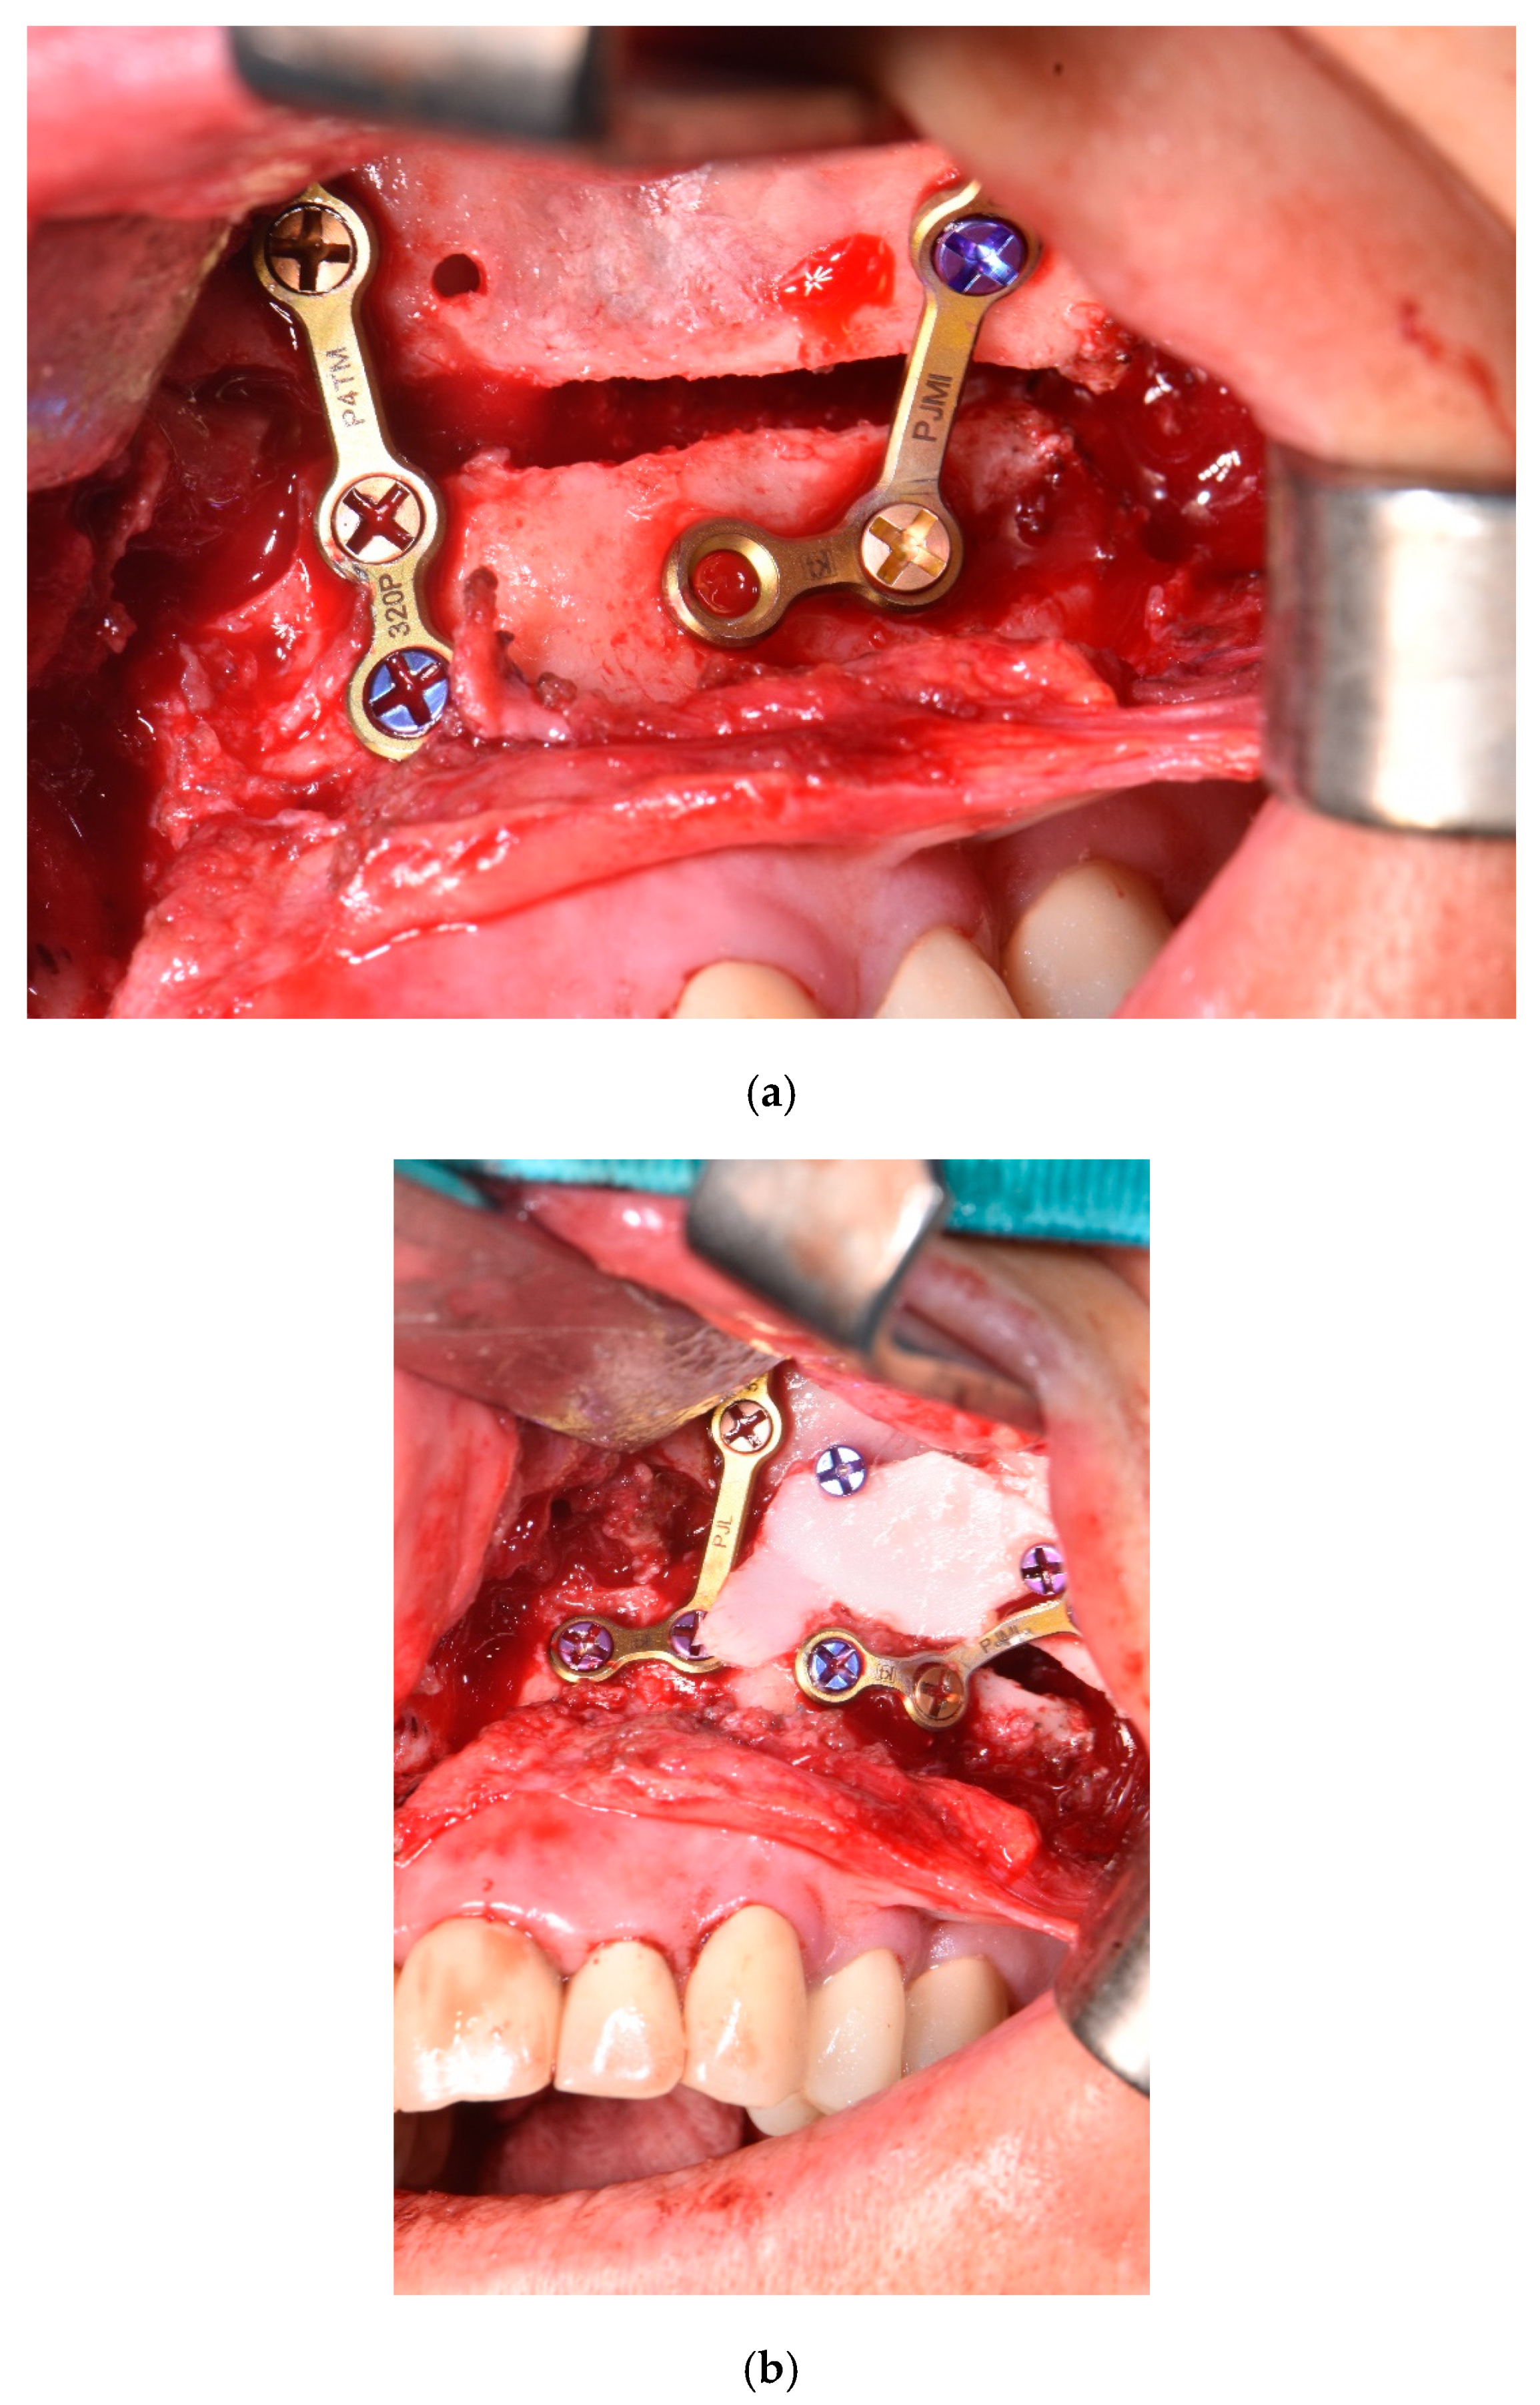

2.4. Surgical Phase